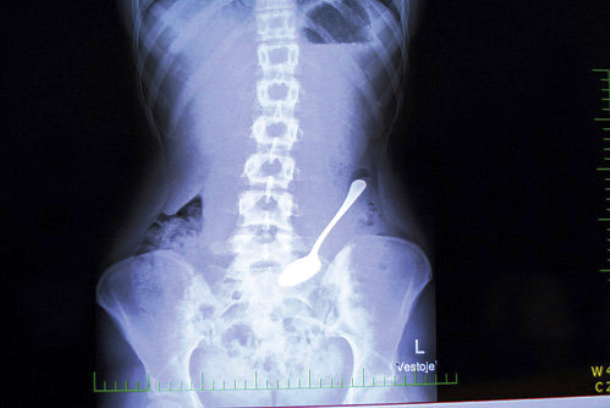

Spoon

A 33-year-old woman had accidentally swallowed a spoon that she had used as a tool to remove the fish bone that was stuck in her larynx. She had to be operated to remove it.